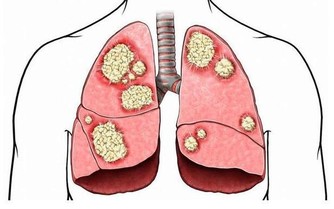

▼3. 指甲粗厚

這可能也是受到了真菌感染,但除此外反應性關節炎和肺部疾病也會有如此症狀。若你患上皮膚病如濕疹和乾癬,你也會有微黃色、生長緩慢的粗厚指甲。另外一種可能性,是源自於不良的血液循環,比如糖尿病會讓手指和腳趾的血液流動緩慢,而影響了皮膚的品質。